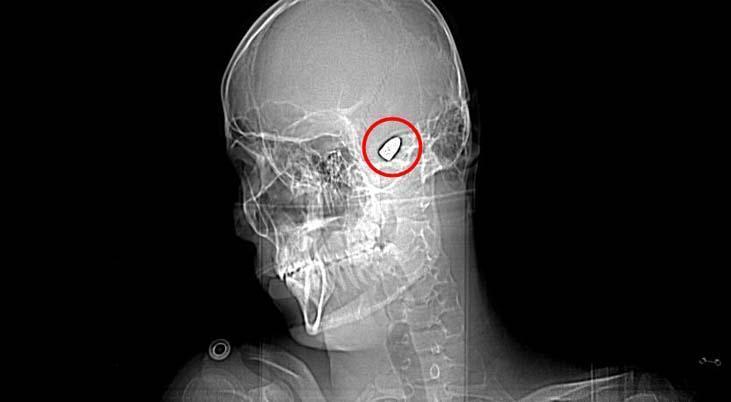

Olay, 5 Kasım 2023’te Bahçelievler Mahallesi 1624’üncü Sokak’ta meydana geldi. Arkadaşları ve ağabeyiyle maça gitmek için konutundan çıkan Yusuf Emre Özbek, birlikte fotoğraf çektirdikten çabucak sonra yere yığıldı. Etraftakilerin hastaneye götürdüğü Yusuf’un çekilen röntgeninde, başında mermi çekirdeği olduğu tespit edildi.

4 gün ağır bakım, 4 gün de serviste tedavi gören Yusuf’un başındaki mermi için hekimler, riskli bölgede olduğu gerekçesiyle müdahale etmedi. Tertipli olarak denetim edilen Yusuf’ta konuşma zahmeti ve sağ el ve parmaklarında zayıflık belirtileri ortaya çıkınca, fizik tedavi süreci başladı.